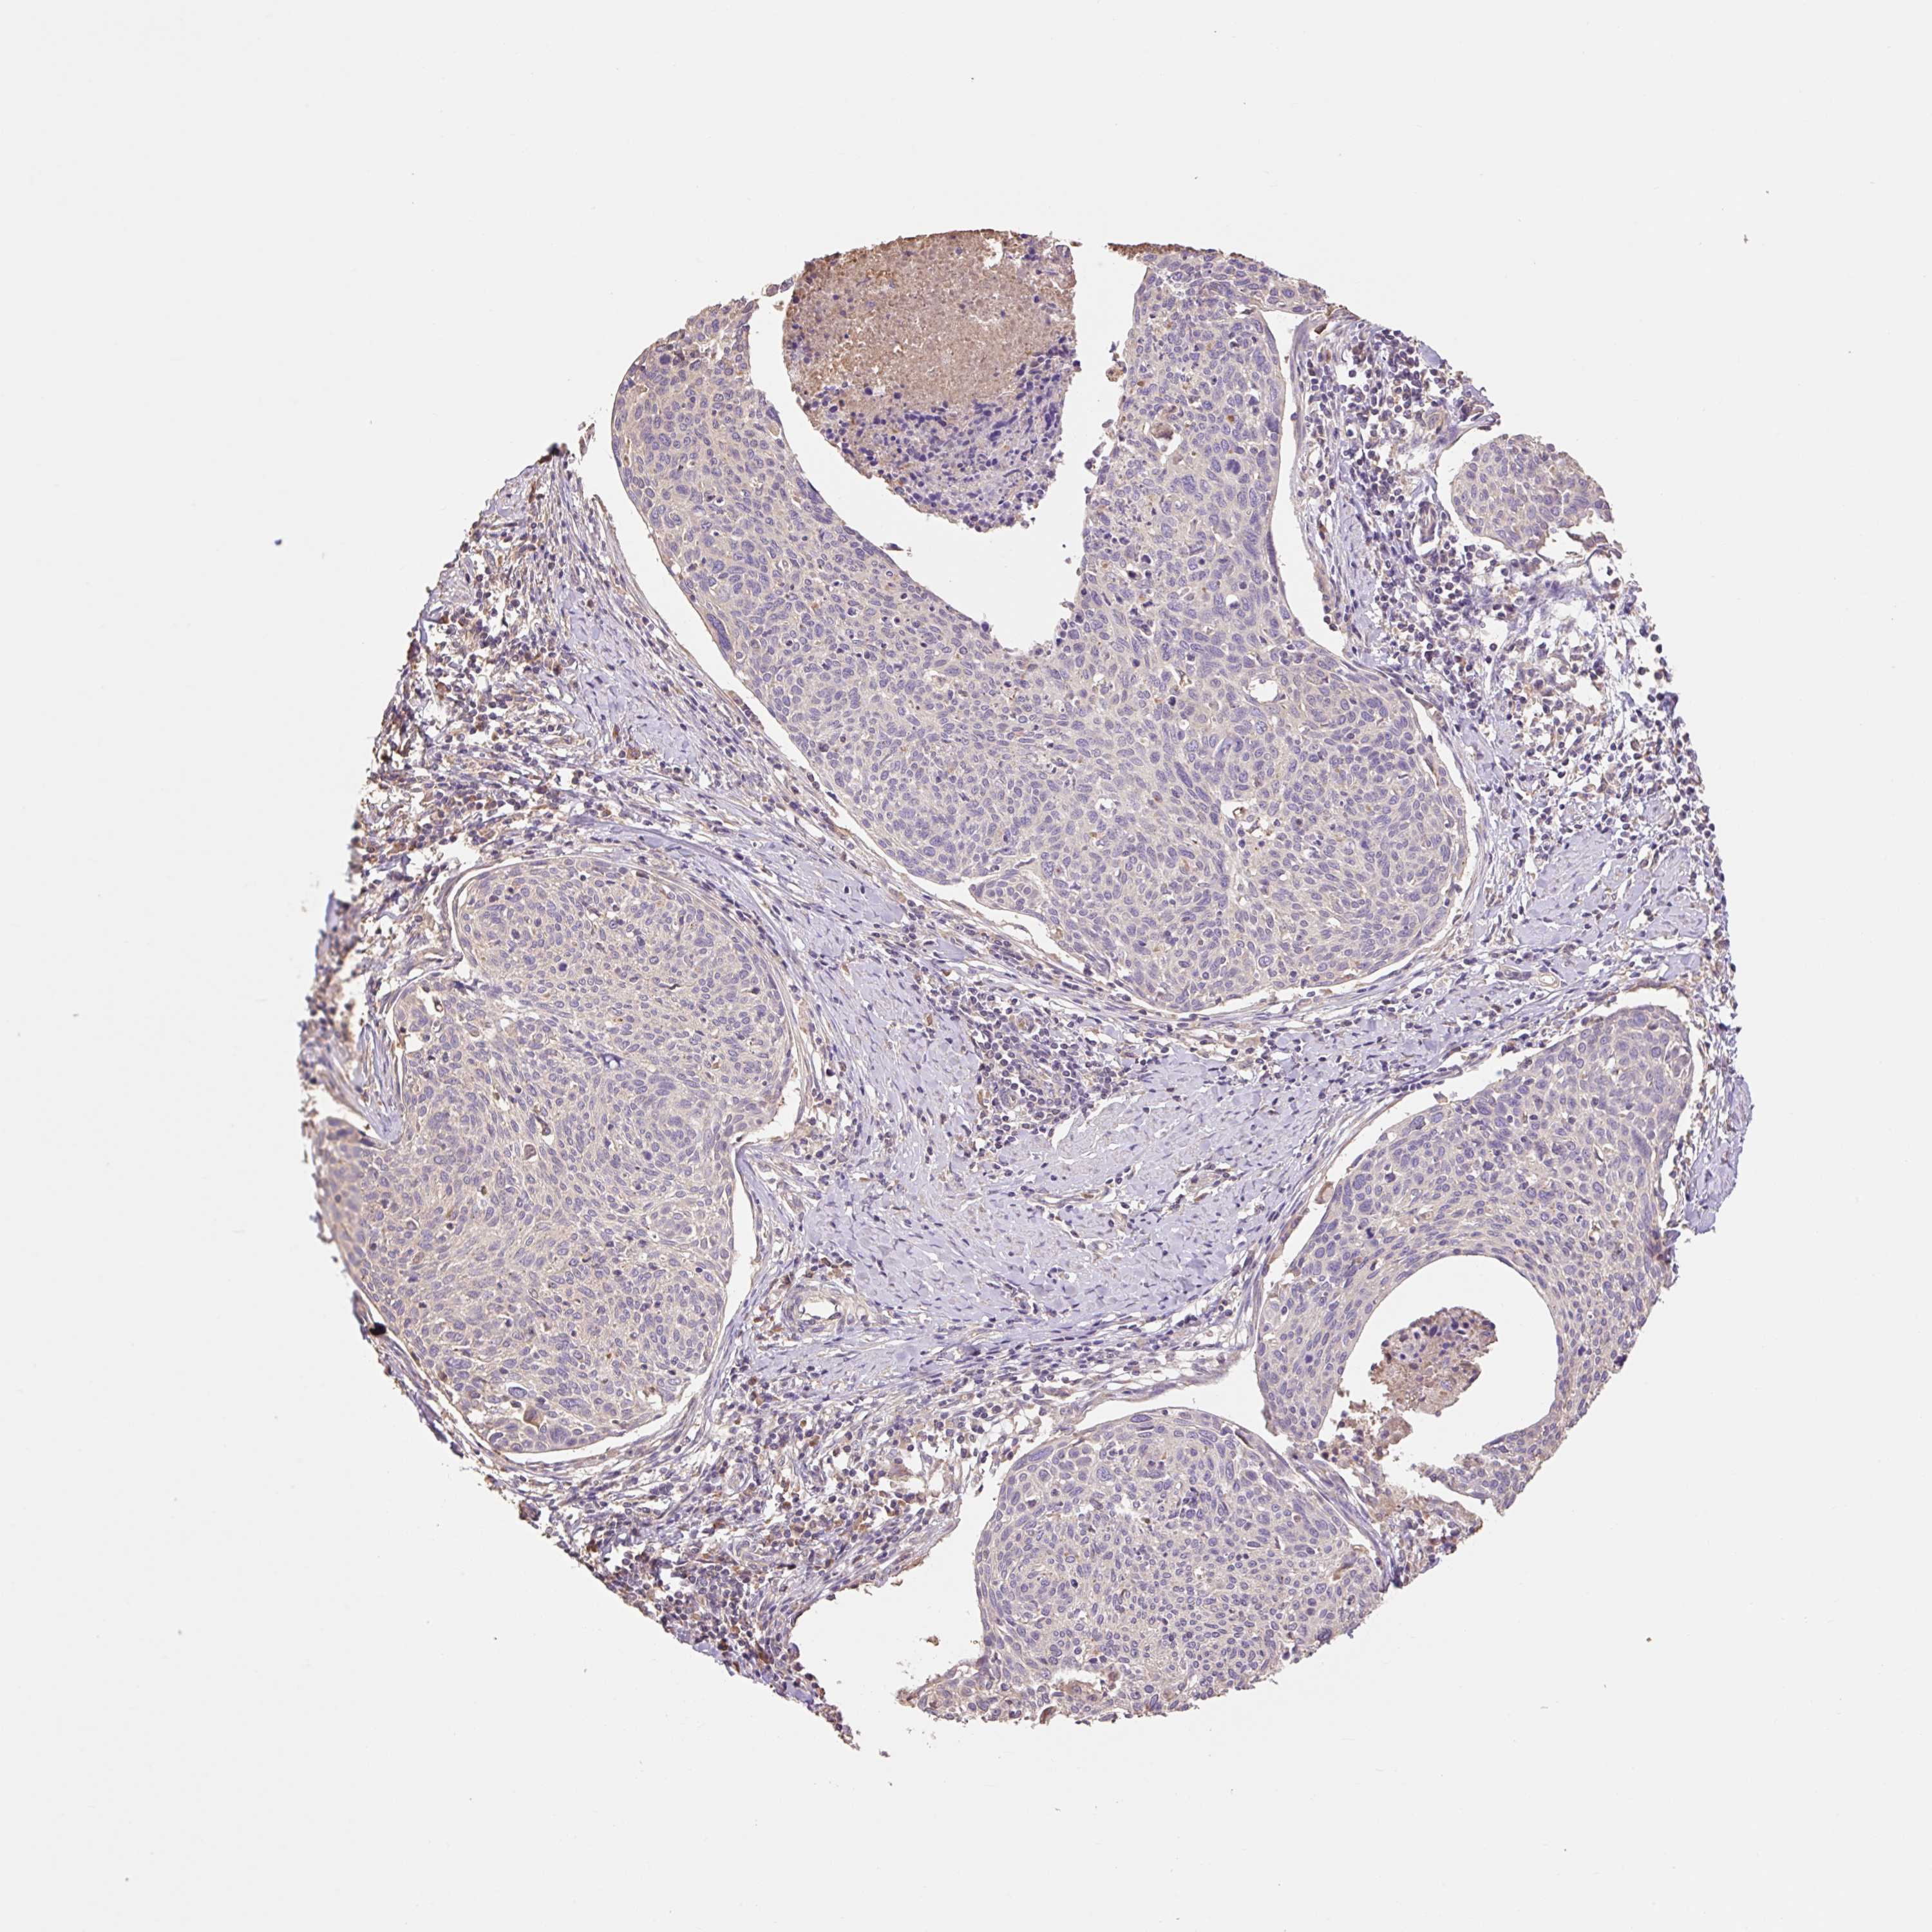

CERVICAL CANCER - Protein expressioni

A mouse-over function shows sample information and annotation data. Click on an image to view it in a full screen mode. Samples can be filtered based on level of antibody staining by selecting one or several of the following categories: high, medium, low and not detected. The assay and annotation is described here.

Note that samples used for immunohistochemistry by the Human Protein Atlas do not correspond to samples in the TCGA dataset.

Antibody stainingi

Antibody staining in the annotated cell types in the current human tissue is reported as not detected, low, medium, or high, based on conventional immunohistochemistry profiling in selected tissues. This score is based on the combination of the staining intensity and fraction of stained cells.

Each image is clickable and will lead to virtual microscopy that enables deeper exploration of all samples and also displays staining intensity scores, fraction scores and subcellular localization as well as patient and tissue information for each sample.

Antibody HPA053415

Staining

High

Medium

Low

Not detected

Intensity

Strong

Moderate

Weak

Negative

Quantity

>75%

75%-25%

<25%

None

Location

Nuclear

Cytoplasmic/membranous

Cytoplasmic/membranous,nuclear

Squamous cell carcinoma, NOS

Adenocarcinoma, NOS